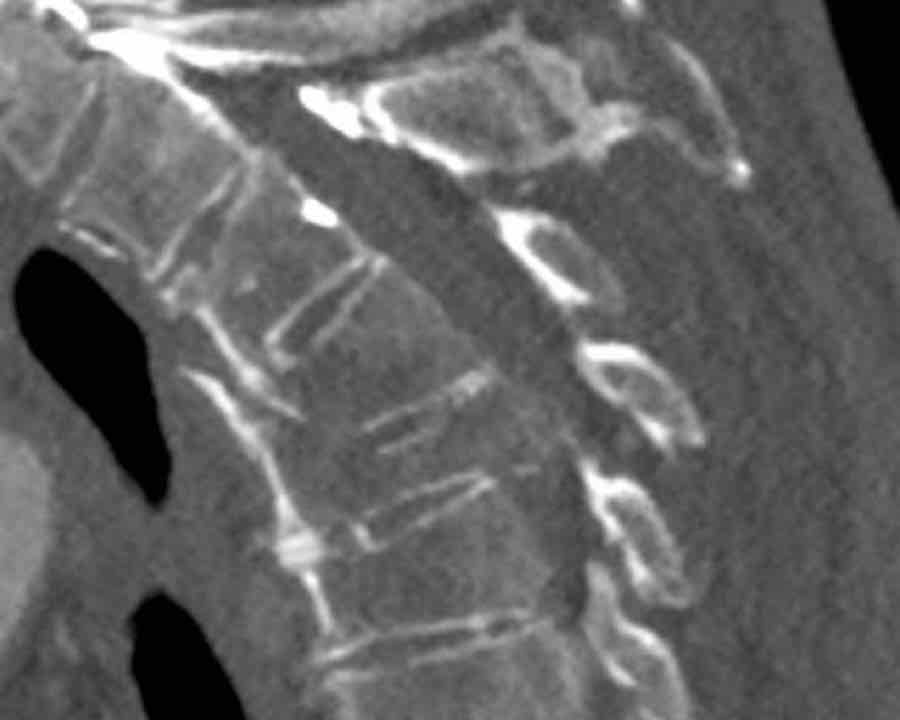

Scroll through images.

What are the findings?

What is the highest AO-type of injury?

Findings

- At a first glance we see a oblique fracture of the vertebral body (A1).

- But as mentioned before, we have to start with the most severe type (C) and work from there.

- So ask yourself: Is there a dislocation in the transverse plane present (yes, look at the white lines) and is there a perched facet joint present (yes, unilaterally on the left side)

Conclusion

Type C + A1 (only upper endplate)